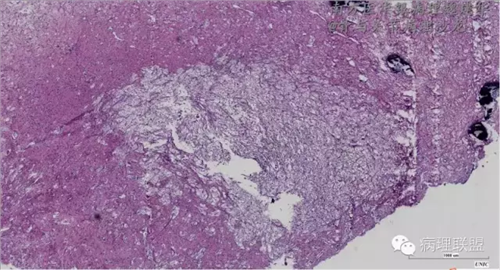

来源于组织细胞的相似性骨病ECD vs RDD 看图说话

病例由南方医华银病理魏建华提供,致谢。